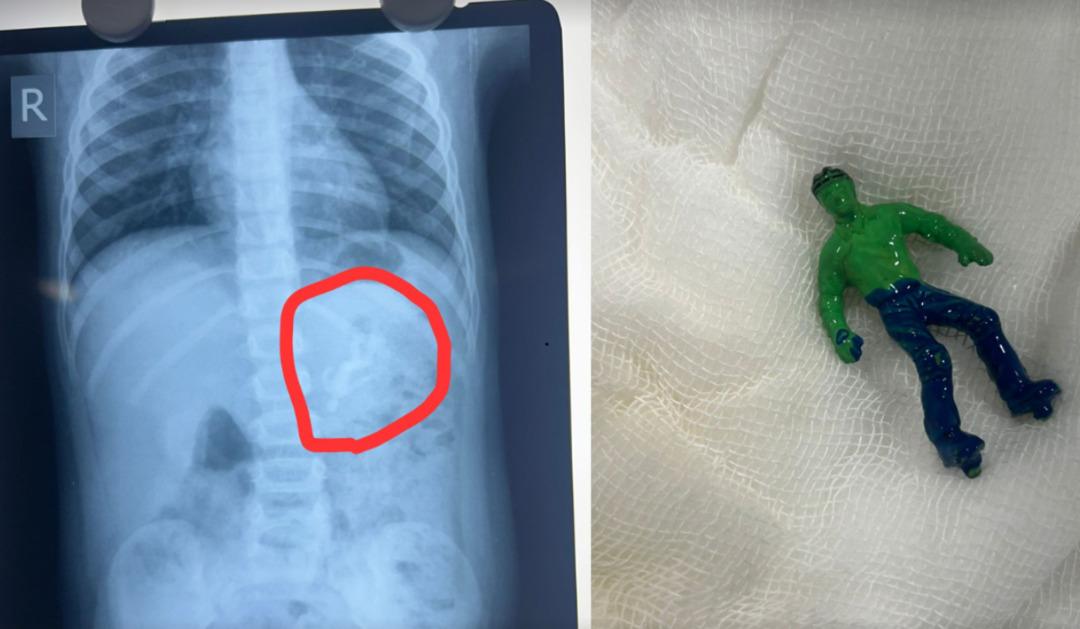

Hindistan'ın Ahmedabad şehrinde yaşanan akılalmaz olay duyanları şaşkına çevirdi. 1,5 yaşındaki Vansh’ın oyun sırasında yuttuğu Hulk figürü, ailesine korku dolu anlar yaşattı.

Kusma ve huzursuzluk şikâyetiyle hastaneye götürülen minik çocuğun röntgeninde, plastik oyuncak figürün kolları, bacakları ve başıyla birlikte bütün halde midesine yerleştiği görüldü.

Midede bütün halde yer alan oyuncağın çıkarılmasının çok zor olduğunu belirten doktorlar, olayın son derece riskli olduğunu aileye aktardı. Son derece zorlu bir endoskopik işlem sonrası oyuncağı mideden çıkarmayı başaran doktorlar, küçük çocuğu sağlıklı şekilde taburcu etti.